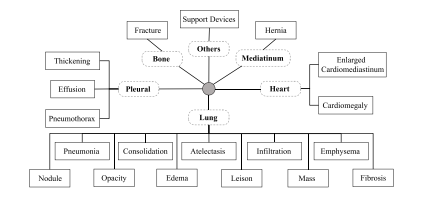

Fig. 6. An illustration of hierarchical dependencies among clinical findings in chest Xrays (sourced from Huang et al. (2023d)). Solid boxes indicate clinical findings whiledotted boxes represent organs or tissues

图6:胸部X光片中临床检查结果之间层级依存关系的图示(源自黄等人(2023d)的研究)。实线框表示临床检查结果,而虚线框代表器官或组织。